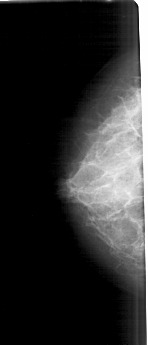

LEFT_CC LINES 5161 PIXELS_PER_LINE 2206 BITS_PER_PIXEL 12 RESOLUTION 43.5 NON_OVERLAY